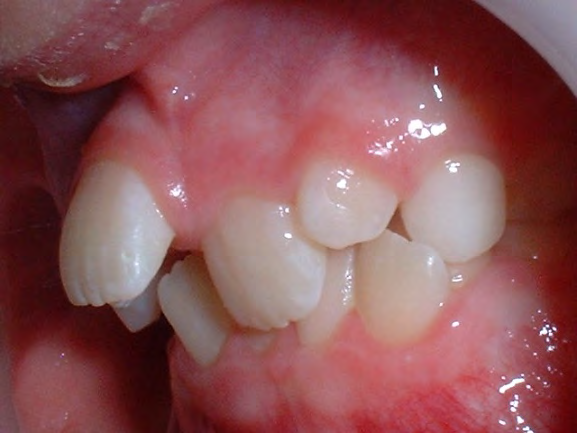

Below are cases treated at Vakresmil without extractions within the last three years. The families had been told, “It is simply not possible for your child to be treated without extractions” by orthodontists. Judge for yourself if that was right or wrong.

The overall aim is to produce the best smile we can — a “beautiful smile”, if you will — without premolar extractions, headgear, facemasks or banded appliances. A smile that both the patient and we at Vakresmil can be proud of.